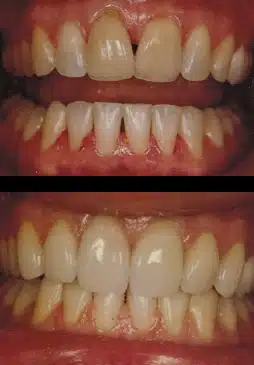

Before & After

One of the most rewarding and exciting new procedures in dentistry today is the system for making your previously loose dentures tight and comfortable. Mini dental implants provide denture patients with the ability to eat, smile, and speak with confidence. In as little as 1 hour, 4-6 dental implants can be placed, and your dentures can be fitted over the implants. The patient leaves the office with a stable denture, which can be used IMMEDIATELY. In addition, placement of these implants results in little to no post-operative discomfort. Many patients who were not candidates for conventional implants because they didn’t have enough bone or because of finances are now mini dental implant candidates.

Made of Hybrid Resin or Zirconia, the removable bridge involves the placement of between 6-10 implants, determined by bone volume and bone quality. This is a fixed hybrid bridge that can be detached by the dentist as needed at recall cleaning visits.